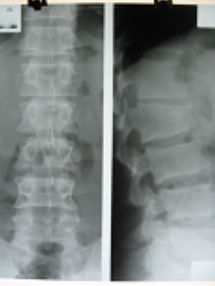

男26y 腰疼2年余,近2月加重,无外伤史。

l2病理性骨折,考虑骨母细胞瘤合并abc可能性大。鉴别:椎体tb,椎体骨血管瘤,软骨母。

首先考虑椎体结核,鉴别终板炎和休曼氏病.

考虑结核,还可见l1-2椎间隙狭窄。

要鉴别就要分清楚死骨、瘤骨/成骨及钙化。该l1/2椎间盘狭窄是由于压缩性骨折而胸腰段曲度后突畸形所致,头二副轴位图像看不到明显骨质破坏,更不要说tb感染椎间盘了。且骨质破坏区太过干净,囊状低密度区边界清晰又有硬化,最重要软组织无改变,病史长达2年无tb症状,不支持感染性/tb病变。

考虑可能性骨母合并abc>骨血管瘤>tb>软骨母。

不像tb,周围没有冷脓肿,这个边缘好像有硬化,

不是结核,陈旧性压缩骨折,椎体前缘软骨结节